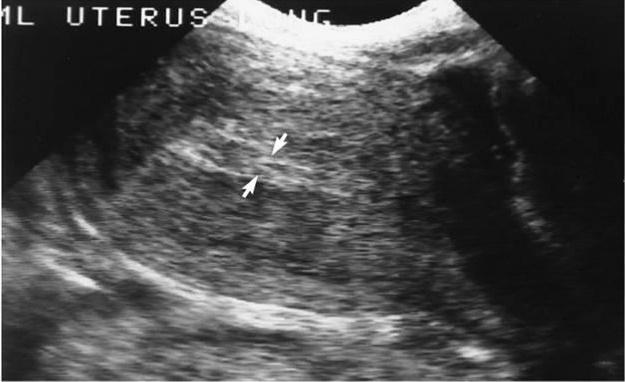

Leiomioma= (Fibroide, Myoma, Fibroma)

Tumor de tejido muscular

Comunes luego de los 35 años

Suelen ser múltiples

Se describen por su localización:

Submucoso - Intramural

Subseroso - Pedunculado

Myomas Uterinos

Por sonografía se ven:

Su apariencia dependerá del grado de degeneración ( de hipoecoicos – isoecoicos y ecogénicos)

Pueden interrumpir el contorno y tamaño uterino.